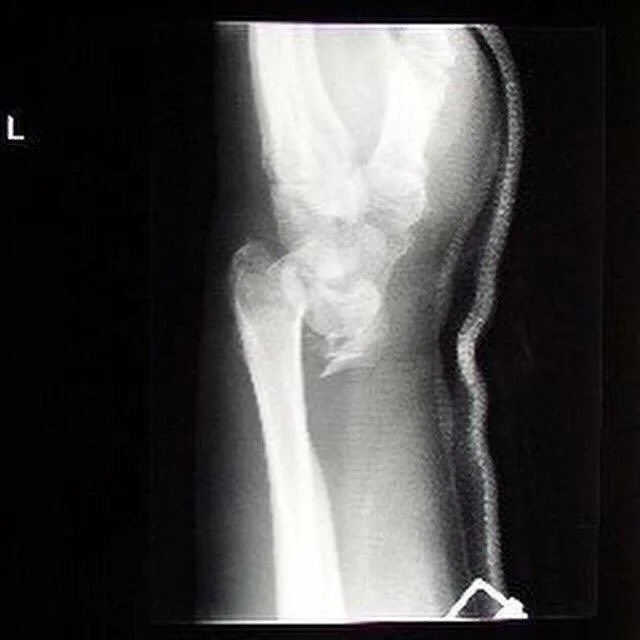

Left Wrist - Rock Climbing Fall

I fell off a cliff rock climbing in Boise at the Black Cliffs. If I remember right, my surgeon said the bone was 3 inches out out of place. It took 10 screws and a plate to put me back together that night (I also took 6 staple is my head that night too).